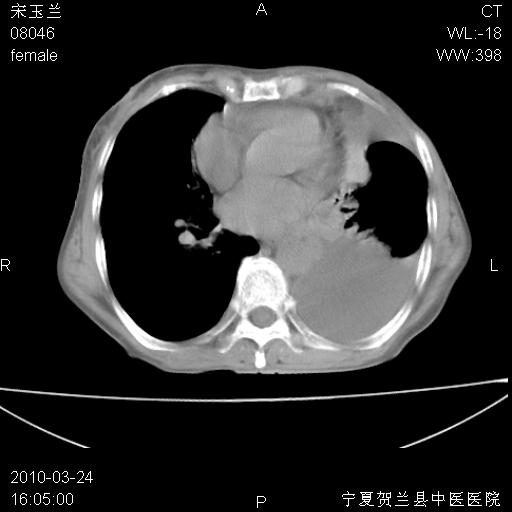

以下是引用zxl51642在2010-3-24 18:49:00的发言:[br]结合乳腺癌术后病史,考虑双肺及纵隔淋巴结多发转移、左侧胸膜转移并左侧大量胸水、左下肺膨胀不全。